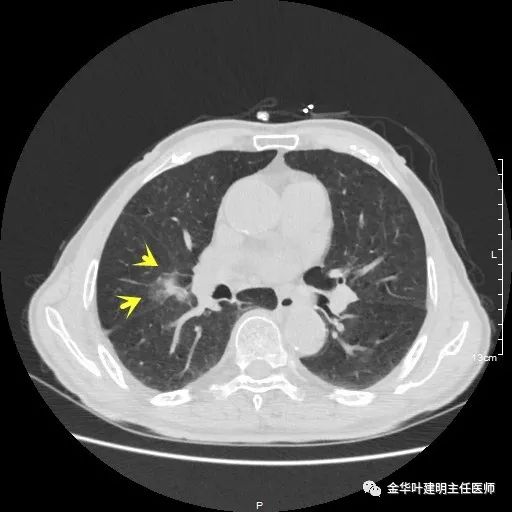

金华的某A,今年已经80岁了,前些天检查发现右下肺部占位,让我会诊。我打开电脑一看图,发现右下肺是典型的实性分叶状的占位,基本可肯定肺癌,余肺仍有多处磨玻璃影及类似慢性炎的病灶,是不是合并炎症?还是多原发肺癌?鉴于其中叶肺门部混合磨玻璃结节边缘略显模糊,为了防止炎性病灶,让其进行了10天的静脉抗炎治疗,但复查靶扫描后发现病灶无任何吸收好转,靶扫描上把细节显示的更清楚了,反而更坚定了我判断其为肺癌的结论。对于这样年纪的多原发癌,我们该如何来进行临床思考呢?治疗该如何建议与决策?当然最后的结果要如实告知患方后,由他们自己决定。

以上示右上病灶,我们称其病灶1。为囊腔型病灶,边缘为磨玻璃影,且轮廓清楚,局部有点状高密度,需考虑为囊腔型肺癌。单纯从单一病灶来看,这样的年纪可以随访或局部切除。